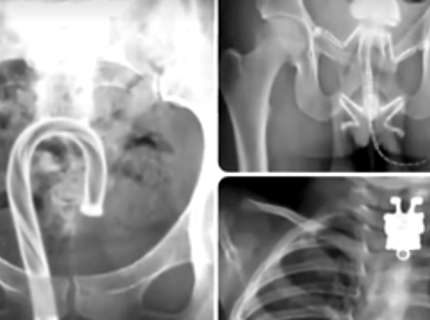

Самые странные вещи, найденные рентгеном